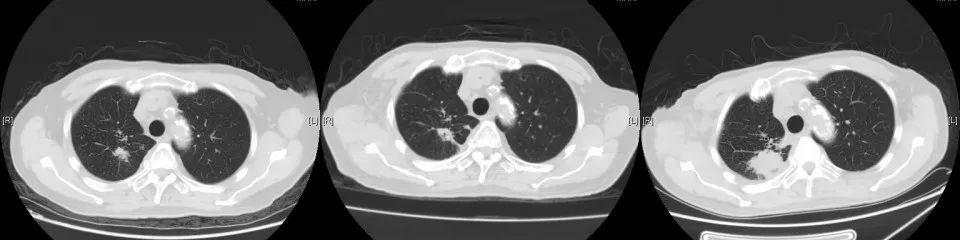

2018年1月复查胸部CT:右肺占位较前增大,余无明显特殊不适。外院再次行肺穿刺活检,病理:右肺组织见癌转移(符合膀胱癌肺转移)。2018年3月14-29日于我院行肺转移灶局部放疗。2018年5月15日-7月11日予标准方案化疗2周期。期间病情稳定。2018年10月复查,局部肺转移灶增大进展、且出现肺新转移灶,评估疗效PD,行NGS全基因检测,根据检测结果,即选用阿法替尼口服行靶向治疗。

2019年9月14日复查,肺转移灶较前增大,考虑靶向耐药,我院予局部穿刺活检,病理:符合尿路上皮转移癌。2019年10月再次行NGS全基因检测,根据基因检测结果,于2019.11月开始选用“奥拉帕利”口服治疗。

CT变化: